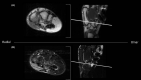

Multifocal chondrosarcoma of the hand: Case report and review of the literature

Few multifocal hand chondrosarcomas have been reported. To our knowledge, this report is the first to describe multifocal hand chondrosarcoma in a patient with no evidence of prior enchondroma, Ollier's disease, or Maffucci syndrome.